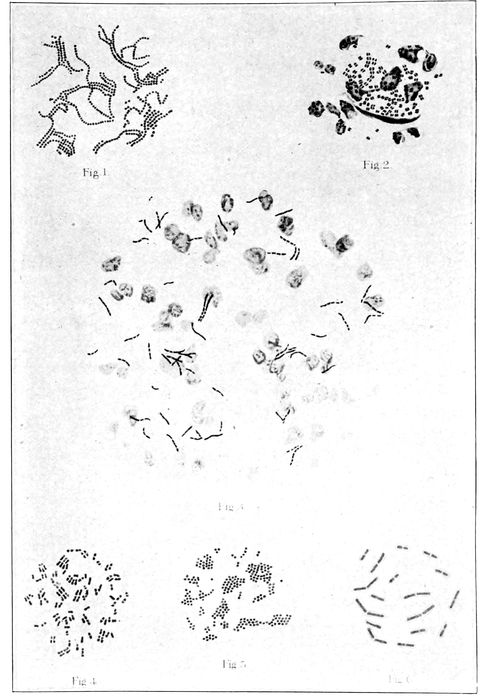

Germs most frequently found in cases of puerperal fever |

256 |